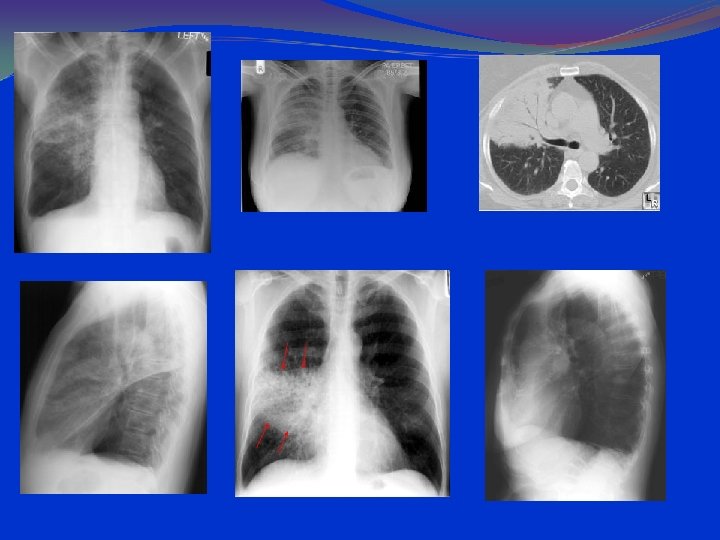

lung hyperinflation with a flattened diaphragm and bilateral atelectasis in the right apical and left basal regions

LABORATORY AND IMAGISTICS Complete blood count (CBC) with white blood cell (WBC) count within normal limits. 2/3 of the children have WBC counts of 10, 000 to 15, 000/μL. Most have 50 to 75% lymphocytes Serum chemistries may be affected in dehydration. Arterial blood gases (ABG) in severely ill patients, with mechanical ventilation. Chest radiographs should include anterior-posterior (AP) and lateral views. Hyperinflation and patchy infiltrates ; these findings are nonspecific and may be observed in asthma, viral or atypical pneumonia, and aspiration. Focal atelectasis Air trapping Flattened diaphragm Increased anteroposterior diameter